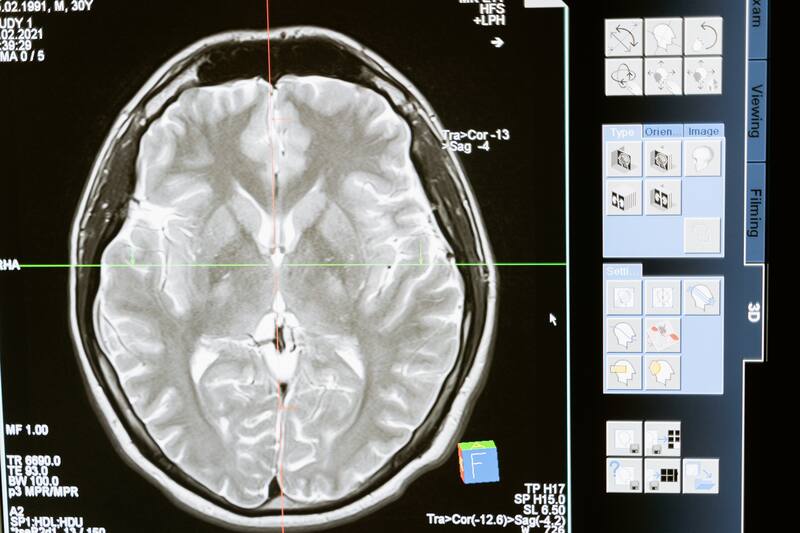

Pese al creciente desarrollo de la tecnología y la medicina, existe una parte del cerebro humano que ningún científico consigue comprender, y es que tiene conexiones complejas que dificultan poder estudiarla.

No obstante, existen enigmas del cerebro que, a pesar del creciente desarrollo de la tecnología y la medicina, todavía no se han podido resolver. En estos misterios entra la “zona incierta”, una región del órgano más complejo de nuestro cuerpo que ningún científico entiende cómo funciona.

Las escasas pistas de los estudios han determinado que la llamada zona incierta, o zona de incertidumbre, es una franja de materia gris que está en la zona central, al interior del cerebro. Tiene al menos cuatro subregiones, que tienen tareas específicas: funciones motoras y viscerales e incluso excitación y atención.